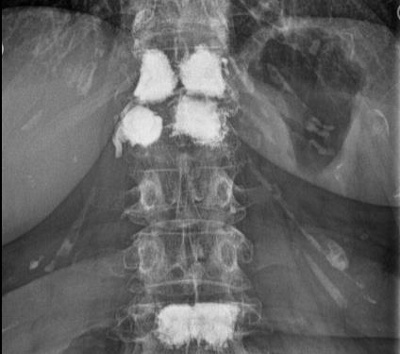

Osteoporose

Osteoporose kann verschiedene Ursachen haben. Die Erkrankung ist jedoch dank fortschrittlicher Medizin gut behandelbar. Zur Diagnose und Abschätzung des Knochenbruchrisikos erfolgt eine genaue Befragung (Anamnese), eine klinische Untersuchung mittels neuester Geräte zur Knochendichtemessung und bei Bedarf auch Gewebeuntersuchungen des Knochens (Knochenbiopsie). Mittels dual energy x-ray absortiometry (DXA) wird die Knochendichte bestimmt.

Zudem sind die Bestimmung des TBS (trabecular bone score) zur Abschätzung der Mikroarchitektur des Knochens und eine Messung der Gesamtzusammensetzung des Körpers (Knochen- und Muskelmasse, Fettanteil) möglich. Neben der Knochendichtemessung können die für den Knochenstoffwechsel wichtigen Blutwerte bestimmt werden.